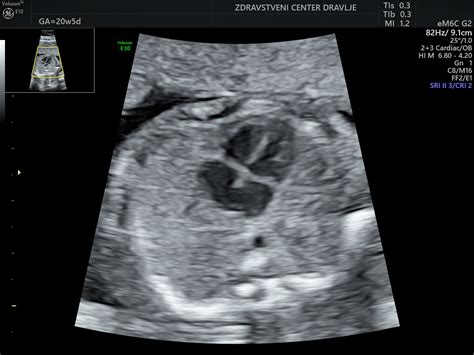

Med 11. in 14. tednom nosečnosti se lahko odločite za ultrazvočni presejalni test za odkrivanje nepravilnega kromosomskega razvoja ploda z merjenjem nuhalne svetline. Ta temeljni in svetovno priznani pregled je podprt z dokazi in služi odkrivanju trisomije 21 (Downov sindrom), 18 in 13 ter večjih razvojnih napak. Ginekolog, ki za opravljanje te preiskave potrebuje posebno tujo licenco, s pomočjo ultrazvoka natančno izmeri nuhalno svetlino - širino špranje med kožo na vratu in mehkimi deli, ki pokrivajo vratno hrbtenico ploda. Posebno pozornost posveti obrazu in nosni kosti: če je le-ta v tem tednu nosečnosti pri plodu vidna, je to zelo dober znak, da je plodov kromosomski razvoj normalen. Pregleda tudi plodovo telo po posameznih delih in odkriva različne razvojne nepravilnosti. Nuhalna svetlina je povečana pri približno 80 % plodov s Downovim sindromom.